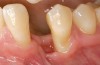

Figure 2  A preoperative retracted anterior view of the failing implant in the site of tooth No. 22.

Figure 2

A 28-year-old Caucasian female presented to the periodontist with a complaint of a mobile implant in the site of tooth No. 22 (Figure 2 and Figure 3). The patient had a congenitally missing tooth No. 23. No. 22 had erupted into site No. 23, leaving a vacancy at site No. 22, and was the reason for the original implant at site No. 22.